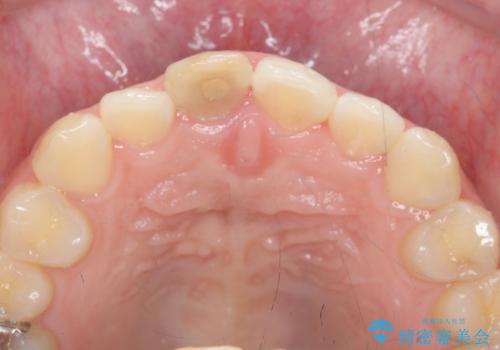

歯ぐきにできものができた 前歯の色調改善

- 歯ぐきに、にきびのようなものができ治らない、と治療を希望され来院されました。

歯髄の検査、X線検査より神経の失活が確認されたので、根管治療・ファイバーコア築盛 ・ジルコニアクラウンの製作、と治療を進めます。

根管治療を行ったことで、歯ぐきのできものは治癒し再発をしなくなりました。